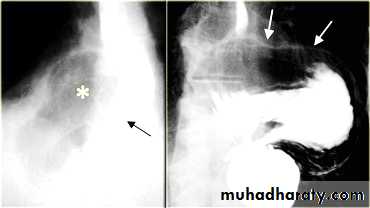

On the far left a traction diverticulum (arrow) due to hilar granulomatous disease. Calcified adenopathy (asterisk).

In the middle a pulsion diverticulum (arrow) due to high intra luminal pressure.

On the right multiple pulsion diverticula (arrows)